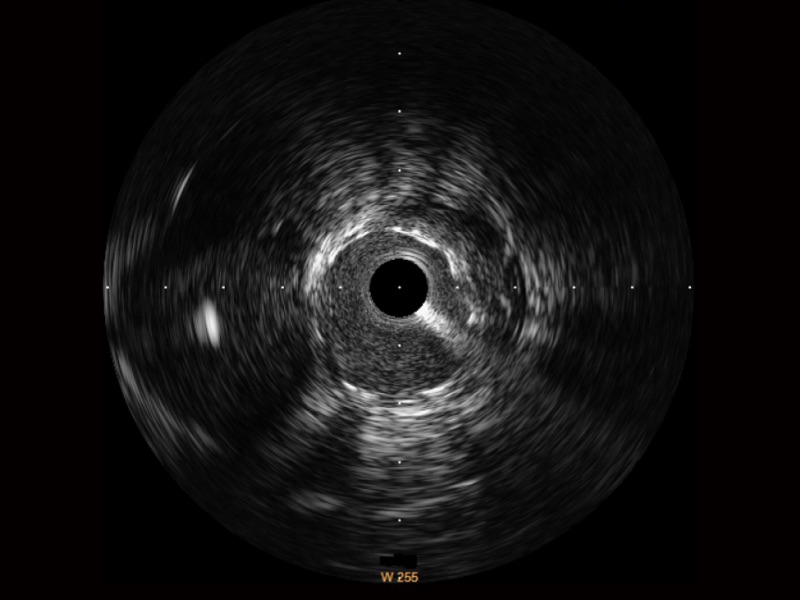

MILE米乐集团官网宽频IVUS图像

传统IVUS图像

对比传统IVUS导管成像,MILE米乐集团官网宽频IVUS图像的近场支架梁显影更细腻,远场中膜外血管仍清晰可辨,兼顾远中近,兼顾分辨力与穿透深度